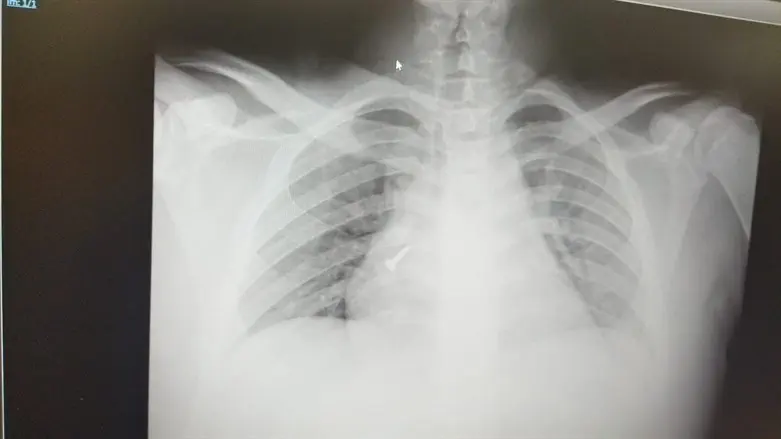

בשל אבדן הכרה זמני, הצעיר לא זכר את אירוע השאיפה שקדם לפציעה. ד"ר מוחמד אמארה, מתמחה בכירורגיה שהיה במשמרת במיון טיפל במקרה והורה על ביצוע בדיקה גופנית מלאה, שכללה בדיקת CT חזה, שאיתרה בריאתו של הפועל בורג באורך 3 ס"מ. ד"ר אמארה הזעיק למקום את צוות כוננות מכון הריאות והצעיר הוכנס בדחיפות לחדר ניתוח.

ד"ר חן חן שועלי, רופאה בכירה במכון הריאות בשערי צדק, שהובילה את הפרוצדורה לחילוץ הבורג יחד עם אנשי צוות נוספים ממכון ריאות וההרדמה במרכז הרפואי, מספרת כי הבורג ננעץ כשראשו מופנה כלפי מטה, מצב שמקשה על הוצאת הבורג.

''לאחר עיון בהדמיה הבנו שאנחנו עומדים בפני אתגר'', סיפרה. ''בצילום ניתן היה לראות כי המנח של הבורג דורש התארגנות רב צוותית. בשילוב כוחות עם הצוות המרדים בחדר ניתוח, טכנאית מכון הריאה, יבגניה זלוטקביץ ואחות מכון הריאה פועה אחיטוב הוחל בהליך שכלל החדרת ברונכוסקופ לאיתור מיקומו המדויק של הבורג, תוך שימוש בלולאה מיוחדת לתפיסת ראש הבורג וחילוצו. המטופל נדרש להרדמה מלאה מאחר שמדובר בבורג די גדול שעלול לסכן את המטופל ולנקב את הקנה, או להתקדם למקום אחר בריאה ולסכן את חייו.